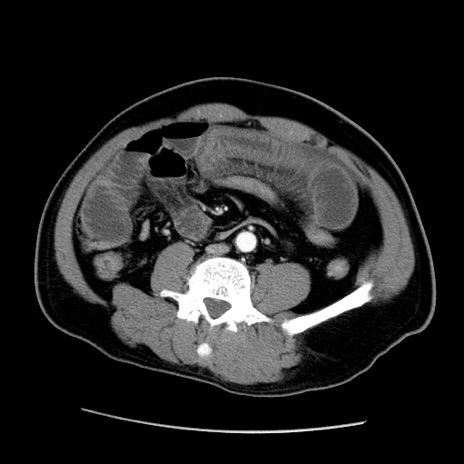

症例22(横断像)

冠状断像

【症例】50歳代男性

【主訴】腹痛

【現病歴】AVMからの被殻出血のため回復期リハ病棟入院中。 本日午後3時頃急に下腹部痛が出現した。

【既往歴】AVM、被殻出血、虫垂炎、高血圧

【身体所見】意識晴明、左半身不全麻痺、会話の理解は良好、36.5°C、腹部:膨隆、全体に板状硬、下腹部正中に圧痛点あり、反跳痛-、筋性防御不明、右下腹部にope scar

【データ】WBC 9400、CRP 0.06